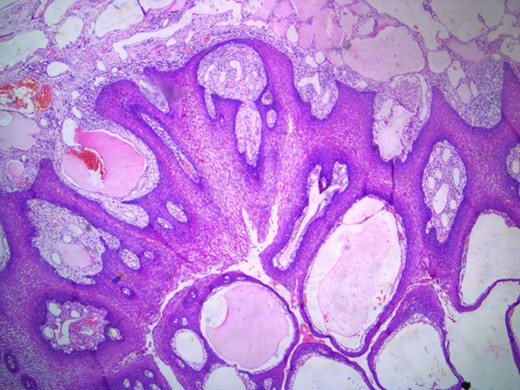

The histopathology report showed mucosa lined by stratified squamous epithelium, with underlying stroma showing dilated vascular channels lined by endothelial cells and containing red blood cells in their lumen confirming the diagnosis of lingual cavernous hemangioma as shown in Figs 5 and 6.

Microscopic appearance of the lingual cavernous hemangioma stained with eosin and hematoxylin at 10 times magnification.